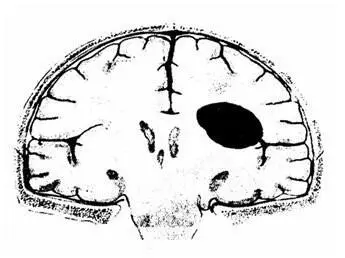

Рис. 10. Схема внутримозговой гематомы